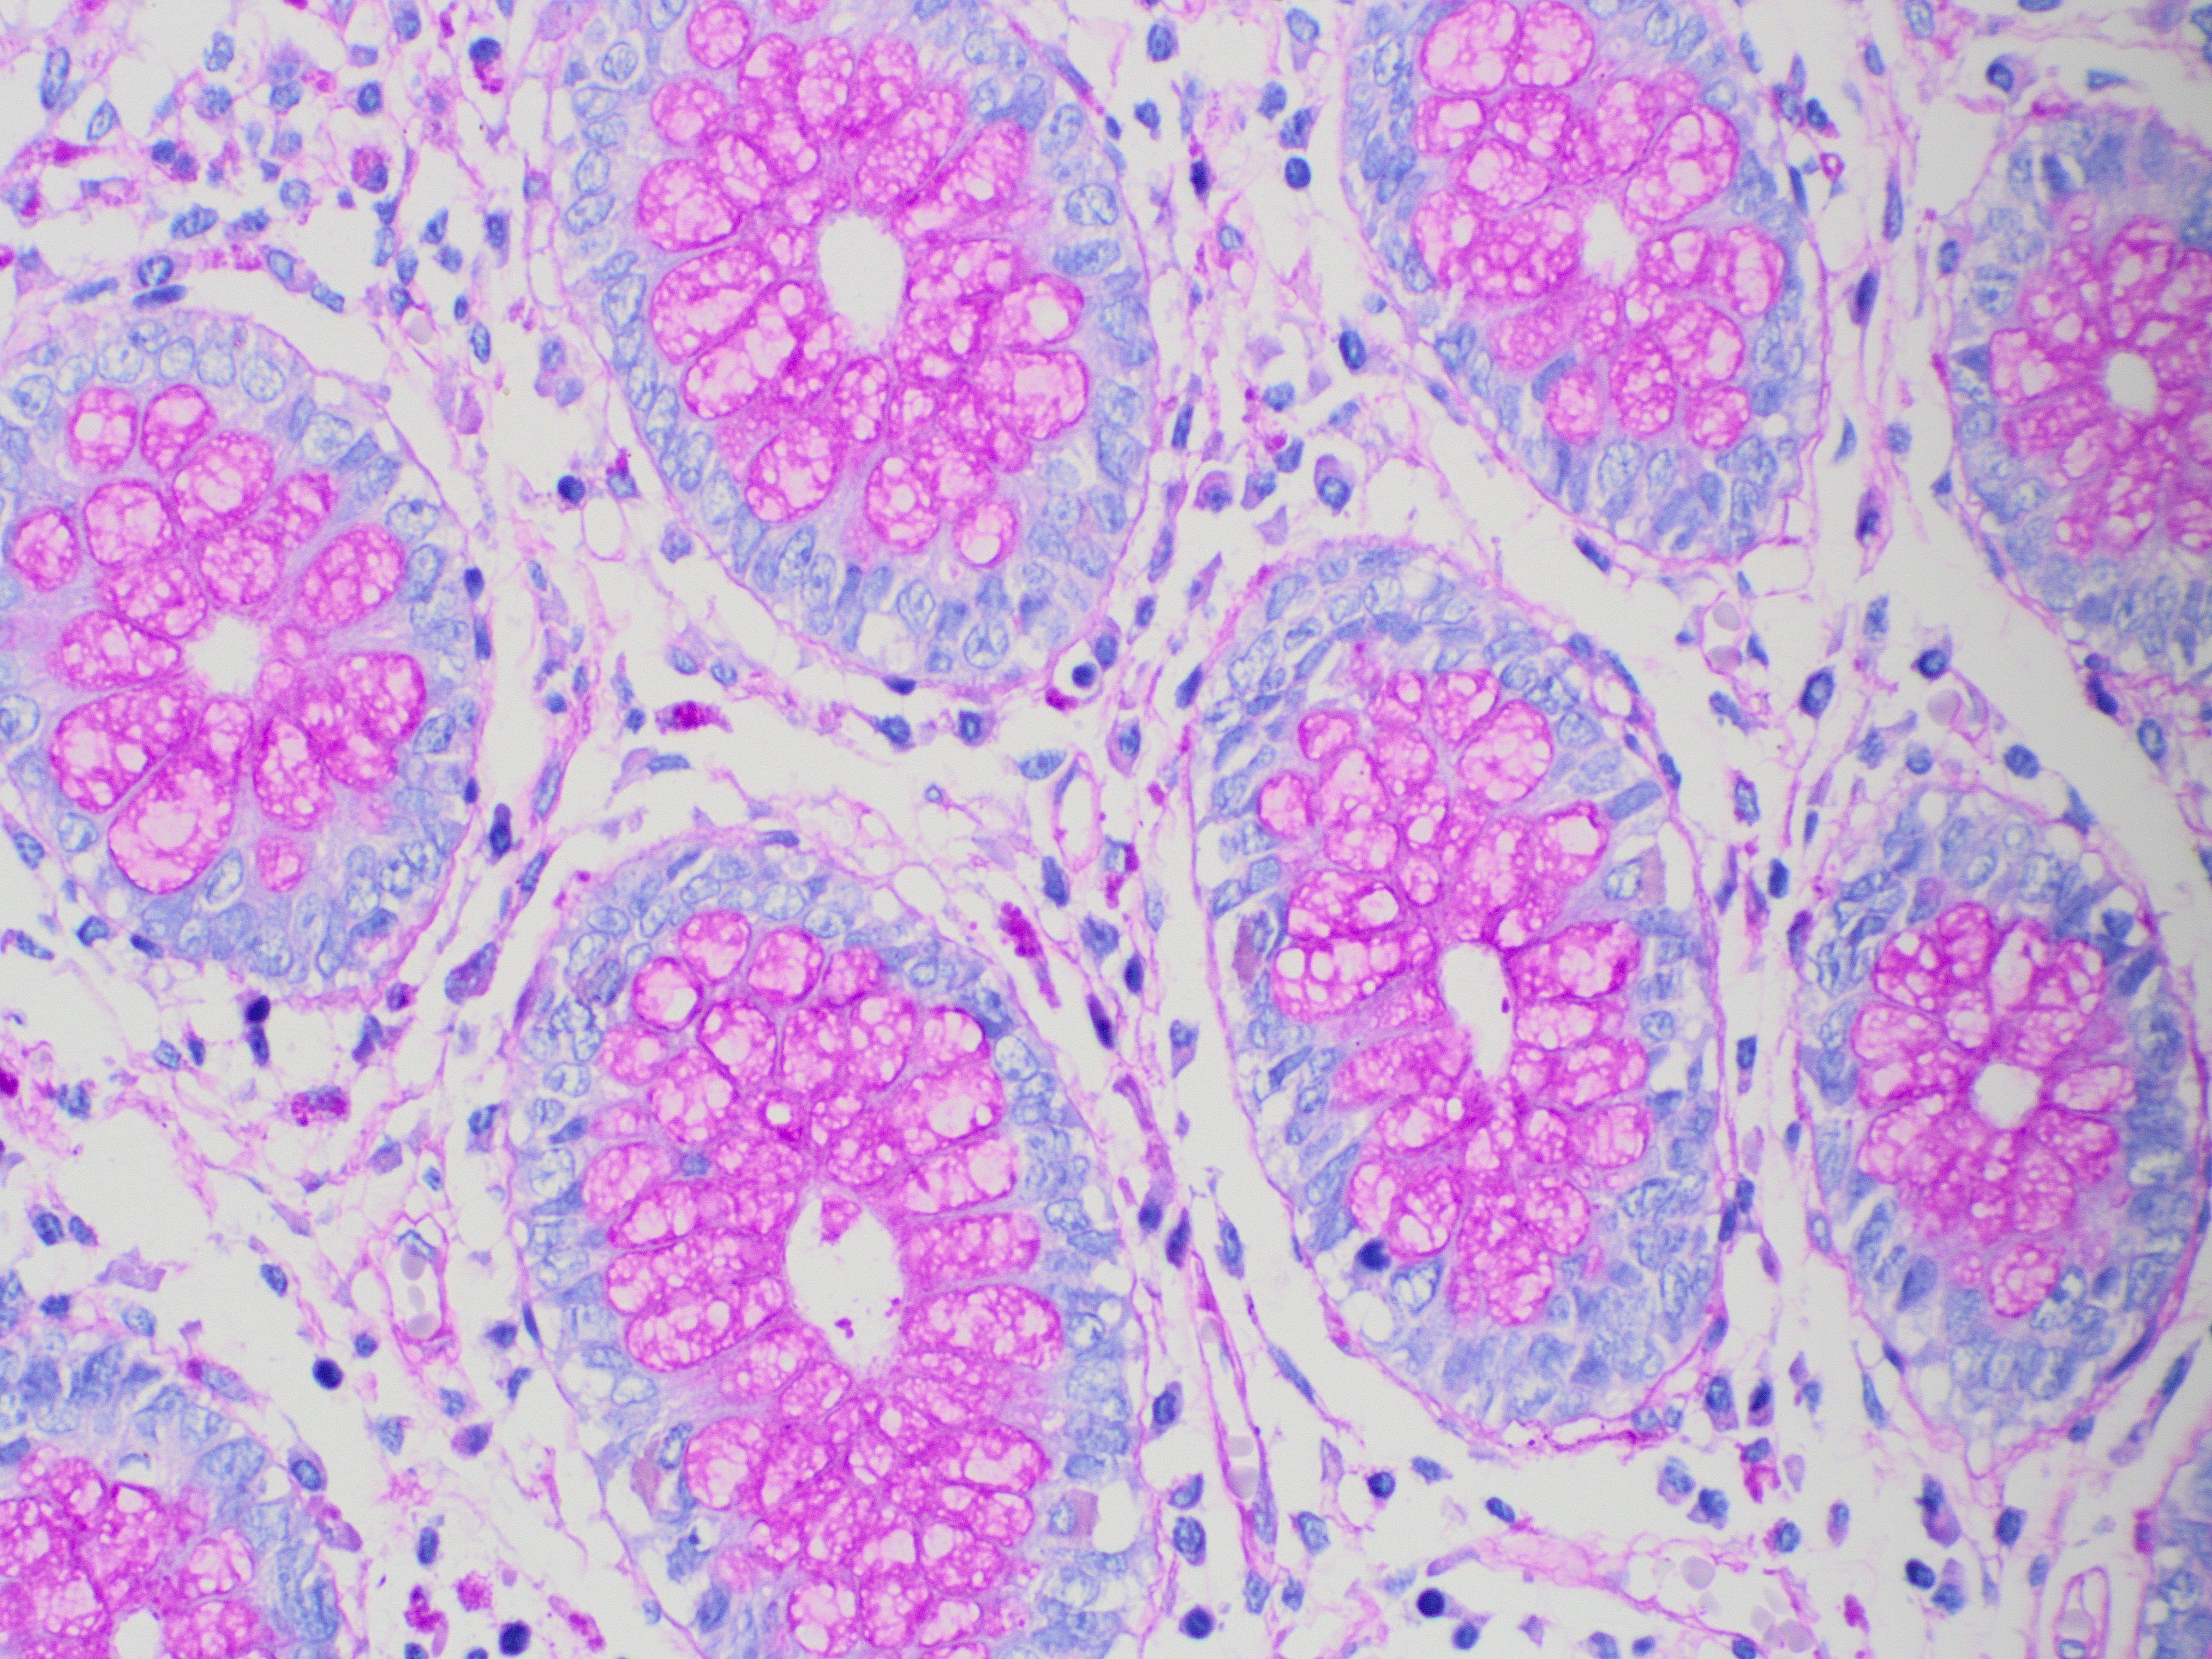

La tinción PAS-Schiff es una tinción ampliamente utilizada en histología o incluso en hematología con frotis de sangre periférica. Esta técnica se usa para identificar polisacáridos, mucopolisacáridos, glucógeno y otras sustancias con grupos glicol en tejidos biológicos y células.

Su mecanismo se basa en la oxidación de los grupos glicol por el ácido periódico, un potente oxidante que los convierte en aldehídos. Éstos reaccionan con el reactivo de Schiff, donde la fucsina que contiene el reactivo se une a los aldehídos, formando un color magenta intenso y revelando la presencia de carbohidratos.